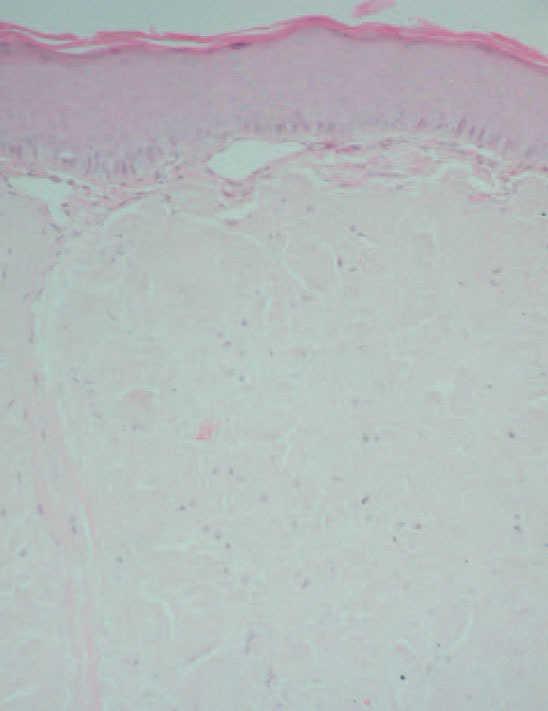

En la exploración, se observó un tumor de 2 cm de diámetro, de bordes bien definidos, en línea media del dorso lingual, de coloración amarillenta y superficie lisa y brillante (fig. 1). Estaba ligeramente infiltrado a la palpación, y no se objetivaba macroglosia ni otras lesiones de interés en el interior de la cavidad oral. El resto de la exploración física se encontraba dentro de la normalidad. Se realizó una biopsia de la lesión que reveló una importante presencia de material amiloide en toda la submucosa como pudo demostrarse mediante tinciones de rojo Congo y tioflavina T (figs. 2 y 3). Asimismo se realizó una tinción para cadenas ligeras que resultó negativa. Con el diagnóstico de amiloidosis cutánea se realizaron pruebas complementarias, entre las que se incluyeron hemograma y bioquímica completos, radiografía de tórax, ecografía abdominal, ecocardiograma, médula ósea, determinación de anticuerpos antinucleares (ANA), 2-microglobulina, factor reumatoide y proteinograma, así como una biopsia de mucosa rectal. Todas estas pruebas se encontraban dentro del rango de la normalidad, y tan sólo se halló una insuficiencia mitral ligera en el ecocardiograma.

Fig. 2.—Depósitos de amiloide en todo el espesor de la dermis. (Hematoxilina-eosina, ×100.)